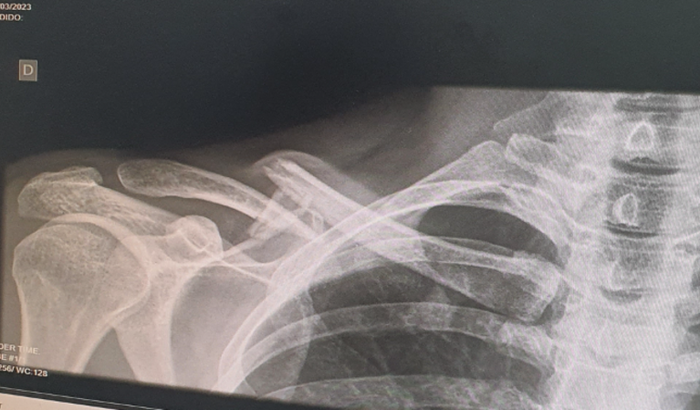

Ela não lembra como caiu, porém como essas provas tem bastante atletas, as pessoas que vinham atrás passaram por cima de suas pernas e pescoço, veio fraturar a clavícula (D).

Sem plano de saúde, ela aguarda uma vaga no UPA da Vila da Mariana para operação.